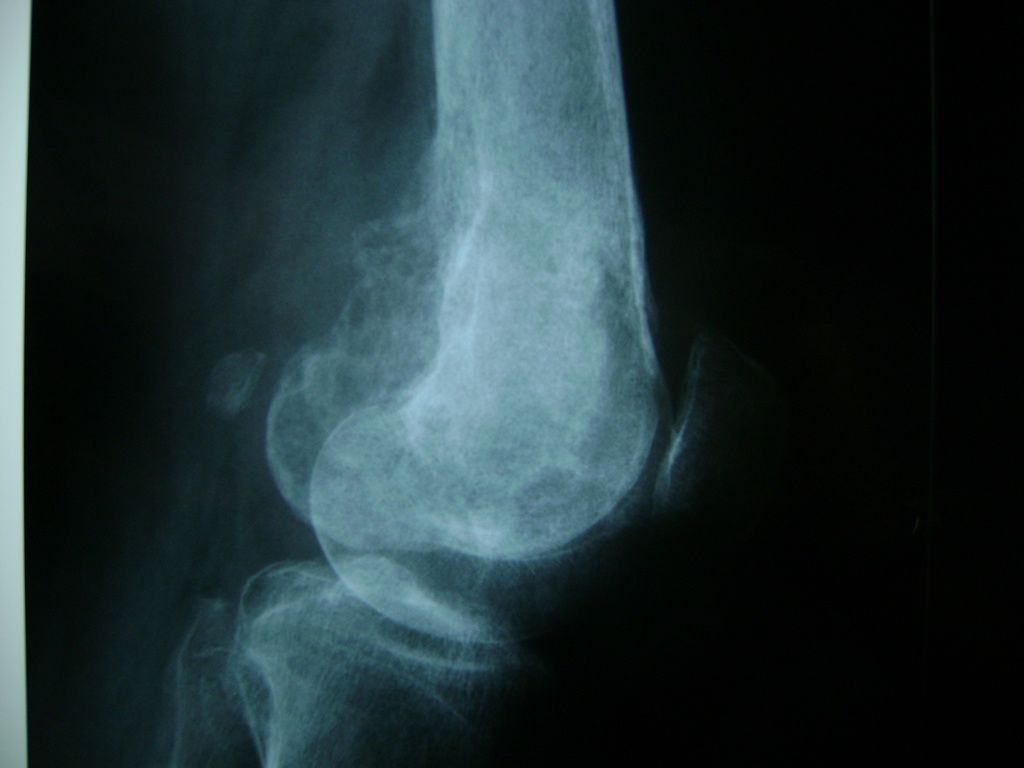

Cirugías de Calcaneo - Rodilla